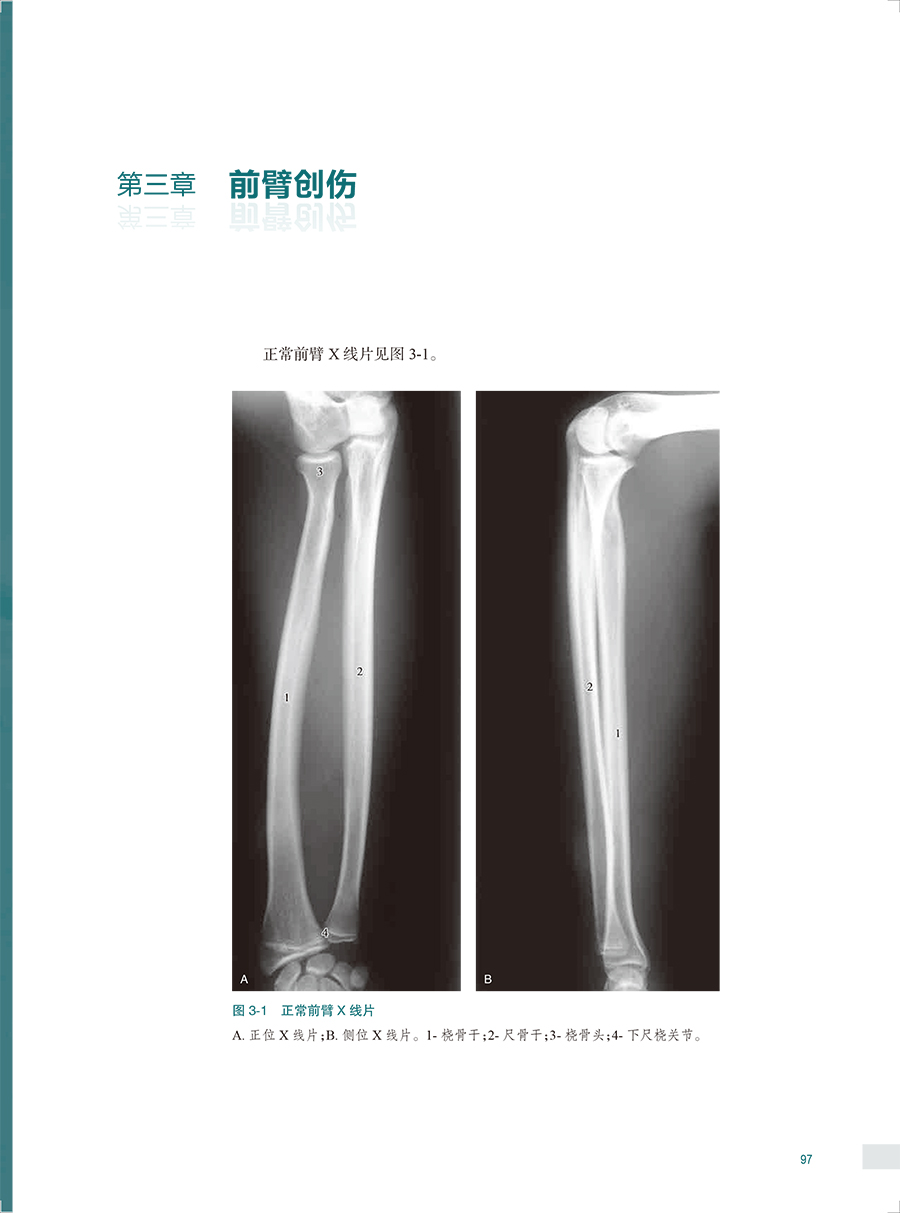

本书是一本系统全面介绍骨关节创伤X线诊断的图谱专著。全书共十六章,前十五章每章基本按创伤类型、诊断要点和鉴别诊断体例编写,最后一章介绍常见骨关节创伤后遗症及并发症。书中共选用1270幅X线照片图,约760个病例,所选图片和病例均具有代表性,可使读者对各部位、各类型的骨关节创伤及其后遗症和并发症有进一步认识,从而提高诊断水平。本书主要供骨科医生、影像科医生使用。